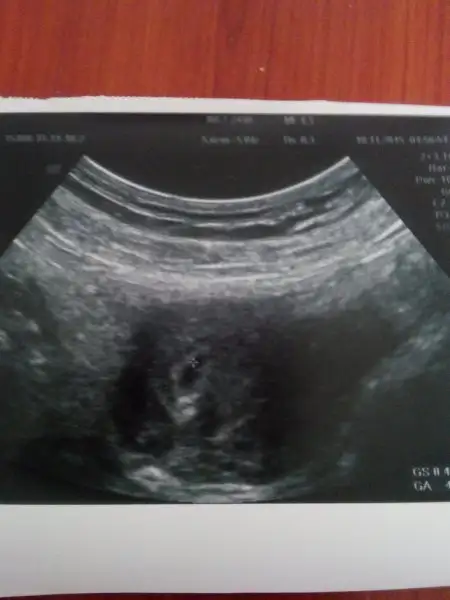

Nefrrtiticim canım allah razı olsun düşünüp merak etmissin gittim kontrole normalde SATA gore 6 haftalık olarak hrsaplamistim fakat Dr. Geç döllenme olmuş 3-4 haftalık dedi keseyi gorduk ama çok küçük dedi 3 gün sonra tekrar çağırdı bakalım ne olcak